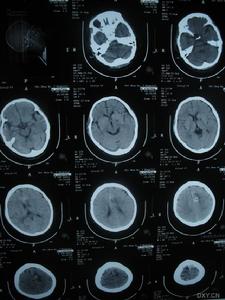

3.必要的實驗室檢查:如血象、靜脈血、尿液、肛指、胃內容、胸透、心電圖、超音波、腦脊液、顱部攝片、CT及MRI等檢查。